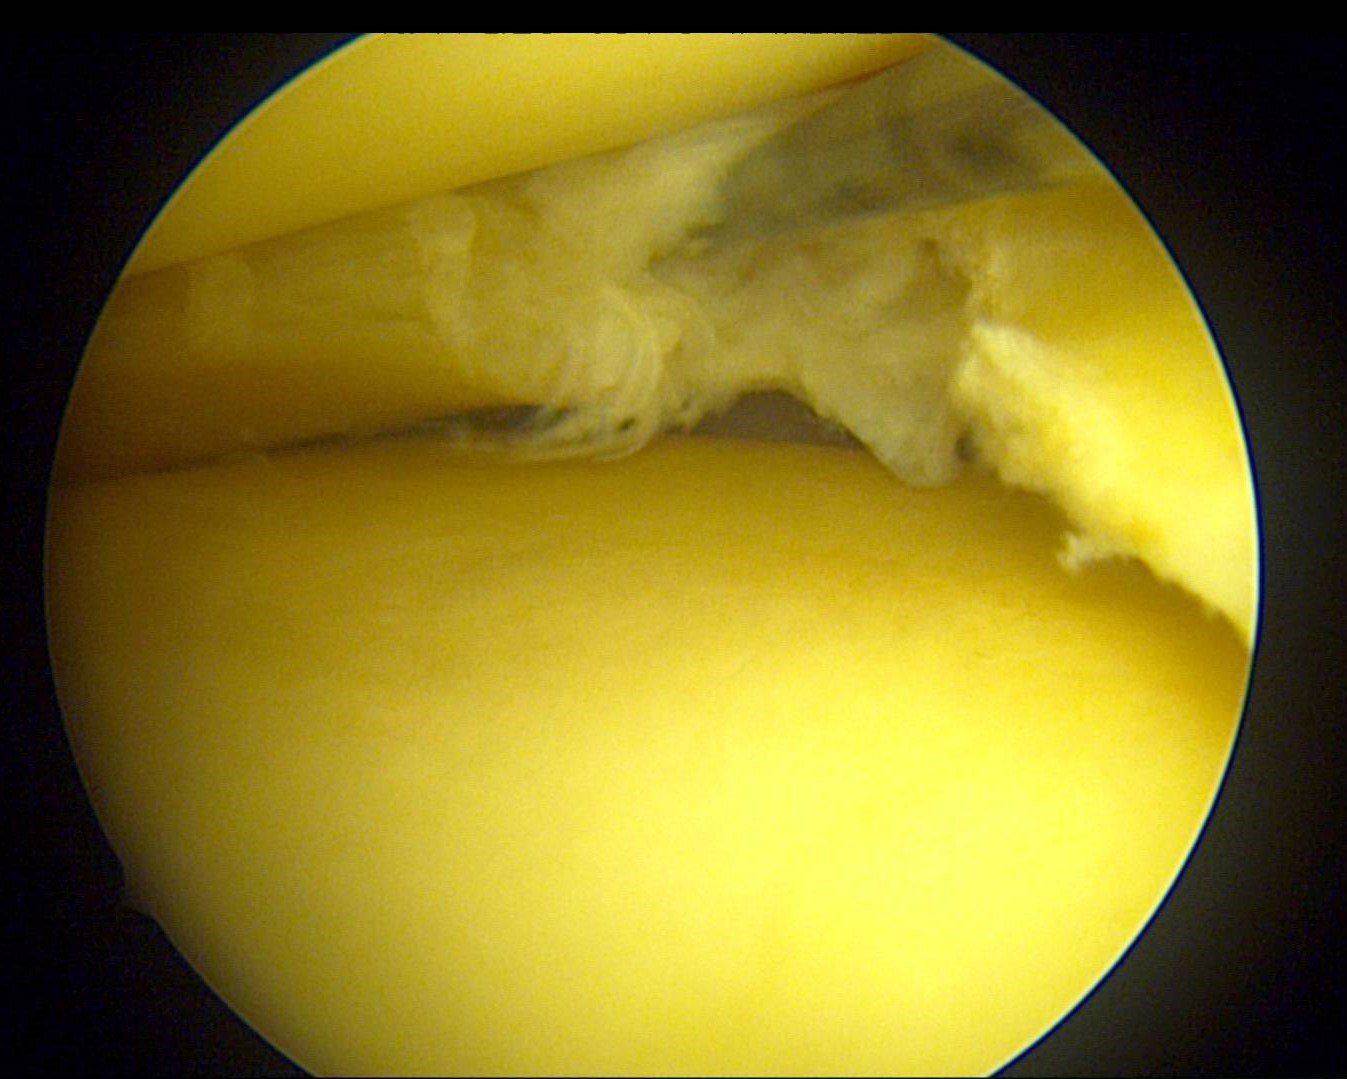

QU’EST-CE QUE L’ARTHROSCOPIE ?

L’arthroscopie consiste à opérer une articulation (ici, le genou) sans jamais l’ouvrir, en y insérant une fibre optique reliée à une caméra très haute définition (4K ou 7K). Une simple incision de 8 à 10 mm suffit à faire passer la caméra. Une autre incision « instrumentale » de 5 à 10 mm permettra le passage des instruments de chirurgie. Grâce à l’arthroscopie, on peut désormais effectuer de nombreuses opérations sans laisser de cicatrice disgracieuse sur le genou.

Il existe grossièrement 2 types de chirurgie méniscale à la Clinique du Genou. Elles sont toujours réalisées en chirurgie ambulatoire :

- Réparation méniscale sous arthroscopie

La suture méniscale est proposée chez des patients plutôt jeunes, actifs ou sportifs lorsque la fissure est située en zone favorable (rouge-rouge ou rouge-blanc). La suture méniscale est un moyen de prévention de la survenue d’arthrose. En réparant le ménisque, celui-ci va reprendre son rôle d’amortisseur antichoc et de guide du genou.

- Méniscectomie partielle sous arthroscopie

Lorsque le ménisque est douloureux, mais que la suture n’est pas envisageable, chez des patients peu demandeurs sur le plan sportif ou plus âgés, on proposera une chirurgie d’ablation partielle la plus économe possible de la zone malade du ménisque. Cette technique a l’avantage de permettre un retour rapide aux activités (marche en plein appui dès la sortie de la clinique, le jour même) et une reprise du travail accélérée.